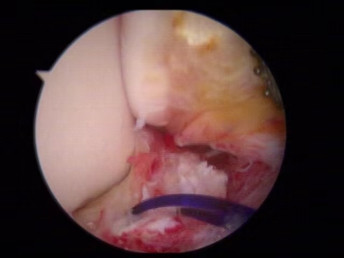

醫(yī)生們?cè)谑中g(shù)中發(fā)現(xiàn),李先生的右踝關(guān)節(jié)軟骨損傷明顯,踝關(guān)節(jié)前方及內(nèi)外側(cè)均有不同程度的骨質(zhì)增生,相互撞擊引起疼痛,同時(shí)距腓前及跟腓韌帶斷裂。手術(shù)醫(yī)生利用磨鉆,小心翼翼將引起撞擊的骨刺一一去除,然后,修復(fù)了損傷的關(guān)節(jié)軟骨,最后,為他完成了距腓前和跟腓韌帶的修復(fù)。

修復(fù)斷裂的韌帶